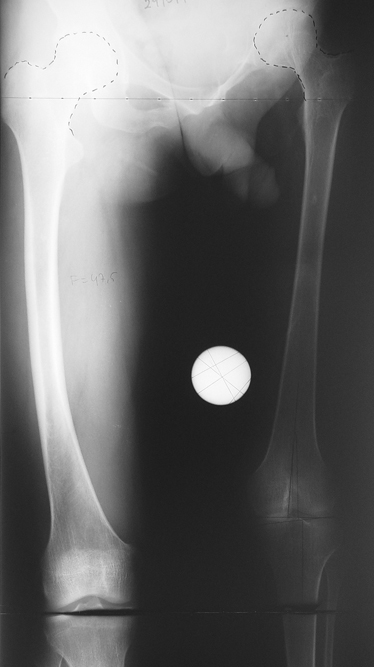

3- POSTTRAVMATİK BACAK KISALIĞI (YANLIŞ KAYNAMA)

Bu Bacak Kısalık tipi bir kırığın kısalmış pozisyonda kaynaması ile oluşur. Bir çok vaka yetişkinlerde görülür ve sadece bir uzatma ile tedavi edilebilir. Ek deformiteler de aynı anda düzeltilebilir. Bu hastaların çoğu çivi üzerinden uzatma veya tam implante edilen çivi ile tedavi edilebilirler.